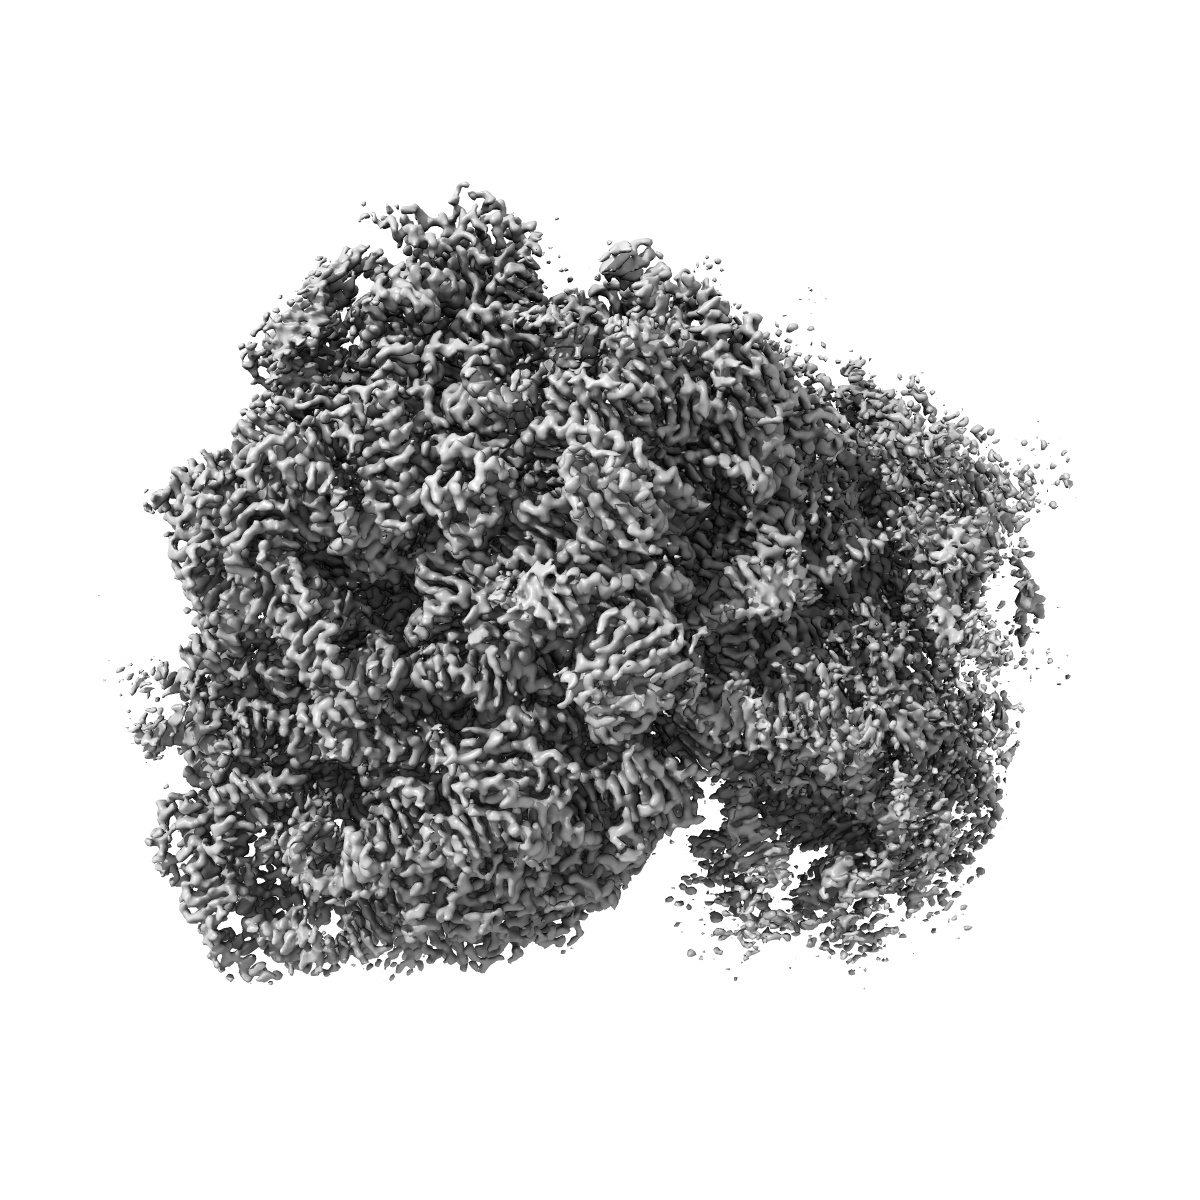

Cryo-EM map of the Candida albicans 80S ribosome in complex with blasticidin s

Single-particle2.67 Å

E-site drug specificity of the human pathogen Candida albicans ribosome.

(2022) Sci Adv , 8 , eabn1062 - eabn1062